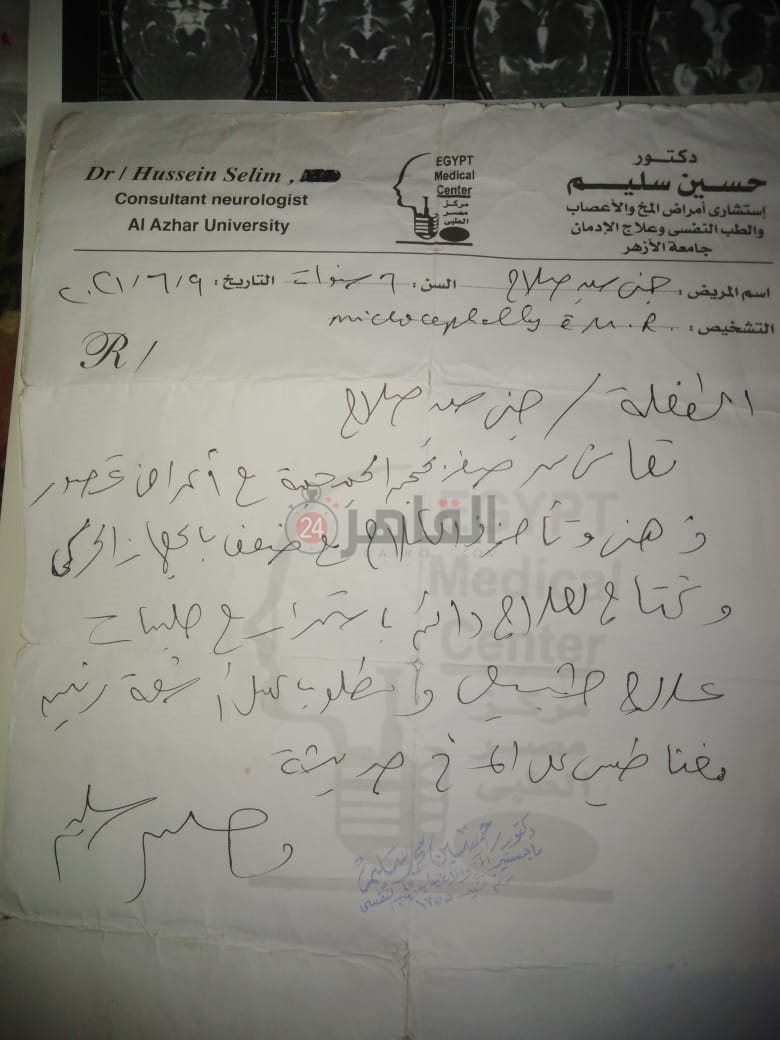

من جانبه، قال صلاح سيد، والد الطفلة جنى صلاح، إن ابنته تعاني من ضمور في المخ منذ ولادتها، نتيجة خطأ طبي، أدى إلى نقص كبير في الأكسجين لديها.

وأضاف في تصريحات خاصة لـ "القاهرة 24": "جنى تبلغ من العمر 6 سنوات، لا تستطيع المشي أو الوقوف على قدميها، نتيجة إصابتها بضمور في المخ منذ ولادتها".

وتابع: "مكنتش بتتحرك خالص، وجسمها طري، روحت كشفت عليها، وعملت أشعة وتحاليل كتير، أتأكدنا إصابتها بضمور في المخ"، مضيفًا:" مش بتعرف تأكل احنا اللي بنأكلها، هي عقلها كويس لكن مش بتتحرك ولا تتكلم".

وأوضح أن الطبيب الخاص بها أكد أن هناك داء خارج مصر يحسن من حالتها، ولكن باهظ الثمن، وتحتاج تناوله بشكل دوري.

واستكمل:" حاليًا تتناول أدوية شرب عادية، لحين توفيرالدولة علاجها من خارج مصر"، مشيرًا: "مفعتش قضية على الدكتور، ورضيت بقضاء ربنا".